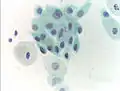

Normal squamous epithelial cells in premenopausal women -

Atrophic squamous cells in postmenopausal women